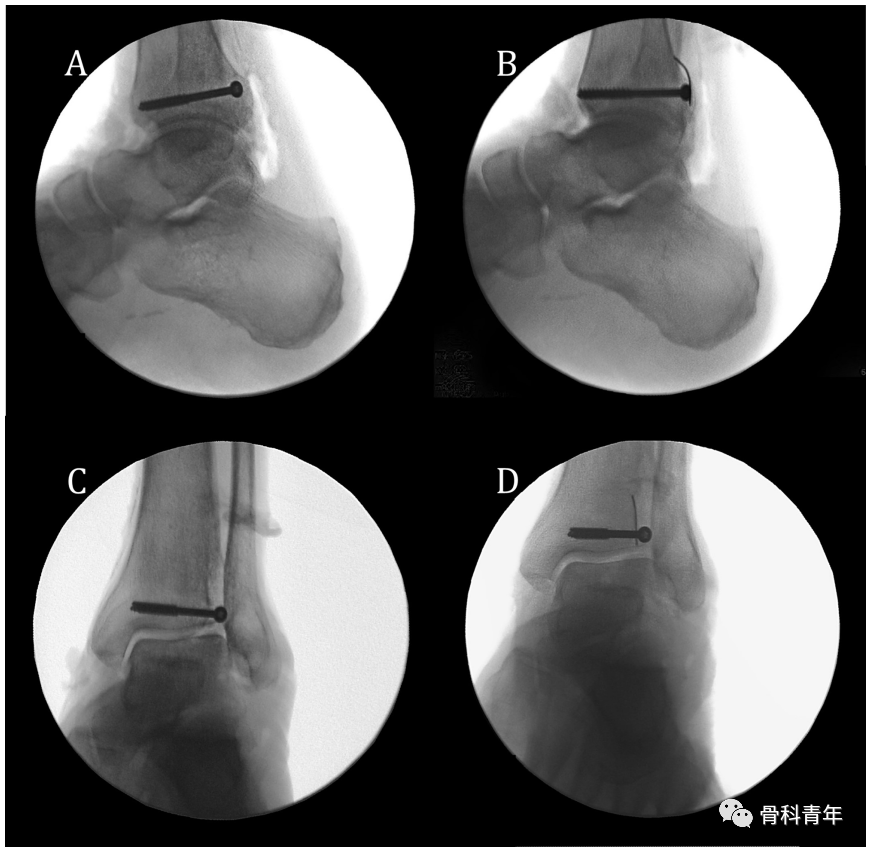

该研究人员对10具标本进行了研究,9例标本螺钉未进入下胫腓内。典型如下:在侧位(A、B)与踝穴位(C、D)上,通过在PVSL线上放置不透光标识,可见后踝螺钉相对于标识的位置,D图上可见螺钉位于标识的内侧。

在一具标本中,后踝螺钉置入关节内,踝穴位上见后踝螺钉位于PVSL的外侧。